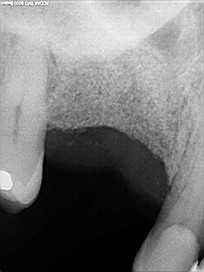

Le bon comblement alvéolaire dentaire est vérifié au bout de quelques mois par imagerie médicale type cone-beam. Puis la pose classique de l’implant peut être réalisée.

Elle consiste à placer un substitut osseux (D’origine animal synthétique ou humain sous forme de granules) au niveau du défaut présent. Ces granules sont stabilisés par une membrane qui a également un rôle de protection. Parfois la mise en place de l’implant dentaire se fait dans le même temps opératoire que la régénération osseuse. La gencive est ensuite replacée et suturée de façon à obtenir la fermeture du site opératoire.

La durée de cicatrisation post opératoire est de 4 à 6 mois et permet une colonisation osseuse au sein du matériau de comblement